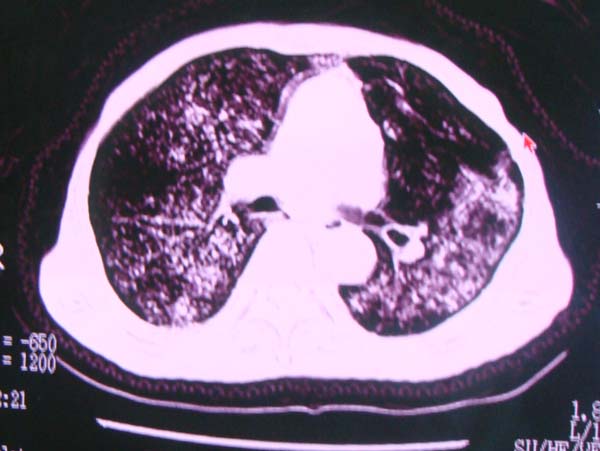

以下是引用zhangzhongshou在2008-2-15 22:25:00的发言:[br]片子照得不清,基本考虑1、细支气管肺泡癌2、亚急性血行播散型肺结核。请结合临床。片子细节显示不清,无法提供进一步意见。

以下是引用杀毒软件在2008-2-15 22:34:00的发言:[br]小叶中心性肺气肿。两肺弥漫性病变,肺泡微石病,过敏性肺炎,尘肺2期,特发性肺纤维化都有可能。[br]不象肺泡癌。